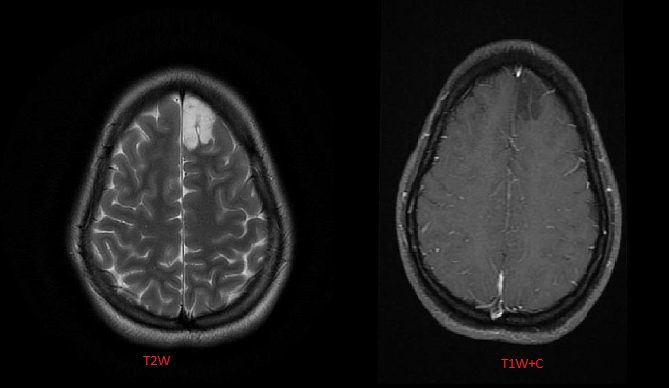

Imaging features of herpes encephalitis?

1. Infection secondary

to herpes simplex virus type 1 (HSV-1) in adults. Patients present with acute onset of fever, headaches, seizures, and/or focal neurological deficits.

2. Characteristically involves the limbic system, including the temporal lobes, insula, inferior frontal lobes, and cingulate gyri.

3. MRI: bilateral, asymmetric

involvement of the cortex and subcortical white matter

with sparing of the basal ganglia. There is edema with loss of gray-white differentiation and local mass effect, typically in

a nonvascular distribution.

Foci of hemorrhage and restricted diffusion are commonly seen. Mild, patchy enhancement may

be seen acutely, developing into gyriform enhancement usually within 1 week.